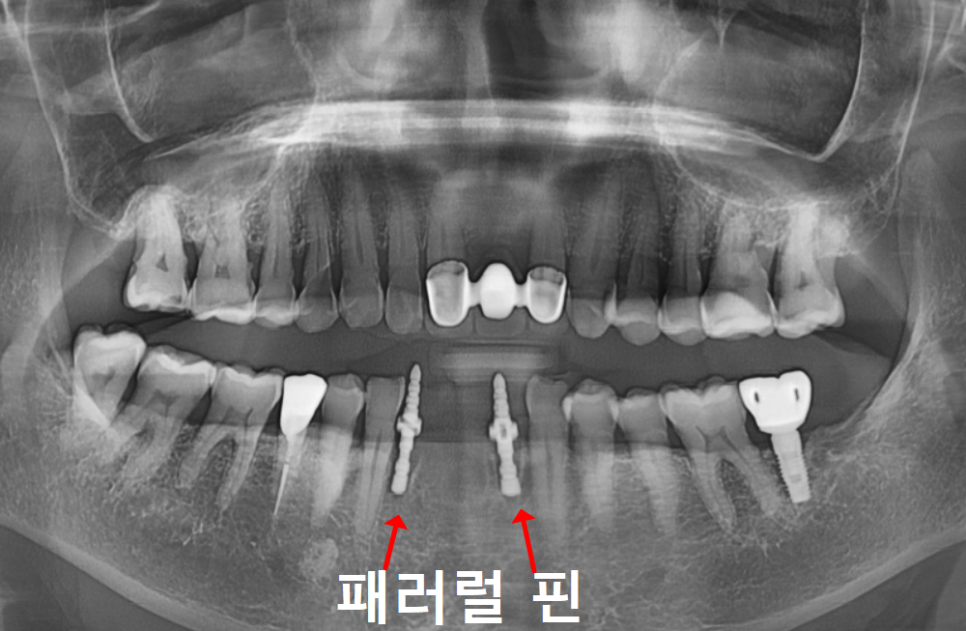

200727(왼) 221022 (오)

2년 전만 해도 뼈 상태가 양호하고

흔들림도 없으셨던 분인데,

2년 후 다시 뵙게 된 환자분은

아래 앞니 2개가 눈에 띄게 솟구치고

심하게 흔들리는 상태였습니다.

원인은 뿌리 염증으로

잇몸뼈가 녹아

지지력이 사라진 탓이었는데요.

마치 흙이 쓸려 내려간 나무가 들썩이듯,

뼈가 없으니 치아가 위로 밀려 올라온 것이죠.

그래서 저희는 ‘패러럴 핀’이라는

도구를 활용합니다.

230609

본격적으로 심기 전,

임플란트가 나아갈 최적의 경로를

미리 그려보는 일종의 ‘나침반’ 같은 역할인데요.

덕분에 길을 잃지 않고

정확한 위치와 각도에 식립을

마칠 수 있었습니다.